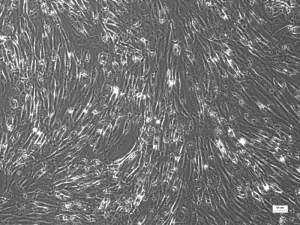

11+ Mesenchymal Stem Cell Culture Pics. Mesenchymal stem cells (mscs) can make several types of cells belonging to our skeletal tissues, such as cartilage, bone and fat. Prockop the discovery of mesenchymal stem cells is credited with alexander friedenstein and associates, who over 40 years ago demonstrated that pieces of bone marrow transplanted under the renal capsule of mice formed a.

Mesenchymal stem cells, but not red blood cells or haematopoetic progenitors, are adherent to tissue culture plastic within 24 to 48 hours.

They can go through relatively many division cycles without losing their expression. They can go through relatively many division cycles without losing their expression. The predominant cell after 2 weeks of culture was. Mscs can be found in the umbilical cord, dental pulp, fat and bon.